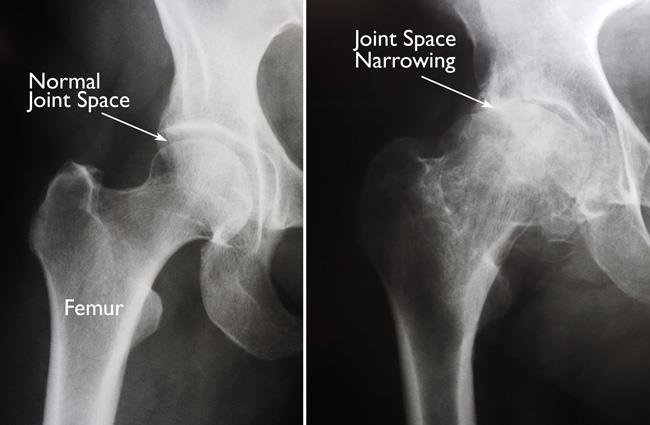

- X-rays. These images help to determine the extent of damage or deformity in your hip.

(Left) In this x-ray of a normal hip, the space between the ball and socket indicates healthy cartilage. (Right) This x-ray of an arthritic hip shows severe loss of joint space.